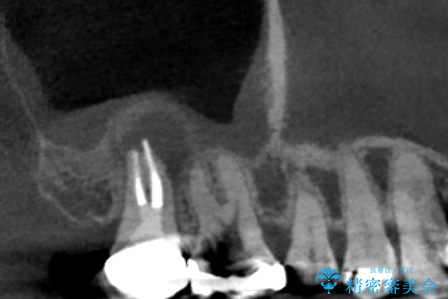

レントゲンと,CT撮影を行なったところ右上小臼歯が虫歯、右上第二大臼歯には根の先に大きな病気がありました。

手前の歯はセラミック治療を行い、奥の歯は精密根管治療を行いゴールドクラウンで治療を行いました。

根管治療はラバーダム防湿を行い、無菌的な状態で治療を行っています。